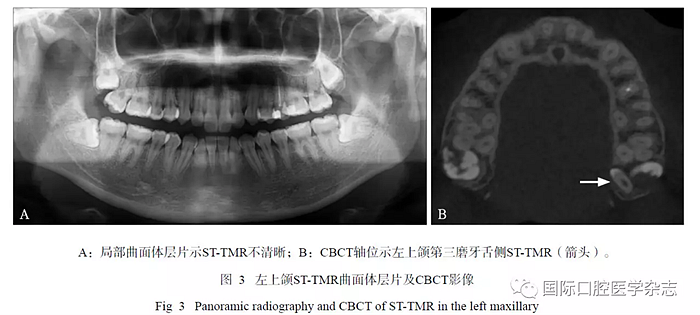

16例ST-TMR患者的CBCT顯示:21顆STTMR中埋伏阻生者占多數(shù)(18/21),3顆萌出(3/21);18顆埋伏阻生ST-TMR多數(shù)與第三磨牙同時阻生(10/18);萌出者2顆位于第三磨牙頰側(cè),1顆位于其方。ST-TMR位于第三磨牙遠中較多(9/21),其余分布在第三磨牙的周圍且變化較大,如第三磨牙近中、頰(舌)側(cè)、根(冠)方;5顆ST-TMR緊鄰上頜竇底壁,1顆進入翼上頜裂。位于腭側(cè)ST-TMR的CBCT較曲面體層片顯示更清晰(圖3)。

目前有較多研究[15-16]已經(jīng)證明,CBCT比二維平片對額外牙具有更高的診療價值,二維平片存在影像的重疊、變形、顯示不清晰,導致誤診或漏診,而CBCT可從三維方向觀察 ST-TMR位置、形態(tài)、大小、病變情況及其與周圍結(jié)構(gòu)的關(guān)系,有利于臨床明確診斷,制定治療計劃。若二維平片懷疑ST-TMR的存在,可以進一步拍攝CBCT來確診。